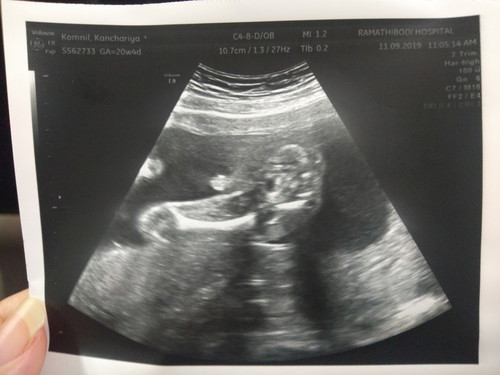

ผลอันตราซาวด์

วันนี้หมอนัดไปซาวด์น้องมาค่ะ ก่อนไปหลายวันเราตื่นเต้นมากเพราะลูกคนแรกก้เลยถามแฟนว่ารู้สึกยังไงเค้าบอกเฉยๆ เราก้เลยไปที่ห้องคนเดียวคุณหมอไม่ให้แฟนเข้าไปแต่พอซาวด์เสร็จ เอารูปลูกให้แฟนดู ตอนแรกหน้านิ่งๆ หันไปคุยกับพยาบาลแปบเดียว หันมาอีกทีเราประทับใจมากนั่งยิ้มอยู่คนเดียว ก็เลยแอบถ่ายมา #ลูกแข็งแรงดีค่ะหมอซาวด์ให้เห็นทุกอย่าง #หมอบอกว่าผู้ชายมีจุ๊ดจู๋